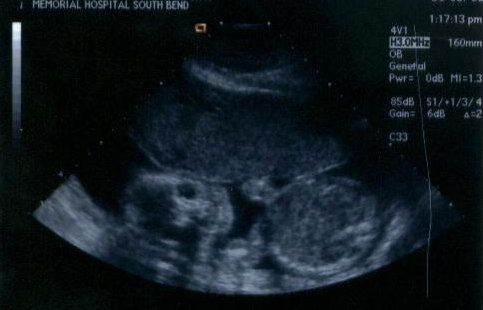

| Here are the pictures from the day we finally found out we are having a little GIRL! I actually find the pictures kind of a letdown after the last couple sets. She's just gotten so big that she doesn't fit well in the screen anymore, so there's not much to see. The second picture, however, is the "gender shot." I don't know enough about ultrasounds to be able to see how that indicates a girl, but the tech seemed pretty certain. (September 16, 2002 - 30 weeks exactly) |